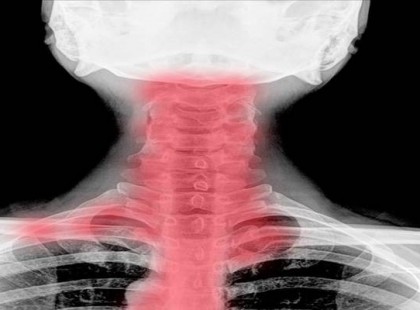

Szédülni szoktál? Zsibbadnak a végtagjaid? Nagyon rossz hírünk van!

A nyaki porckorong, a csigolya deformációja öröklési hajlamtól, a kevés mozgástól alakulhat ki, de a spondilózis az...